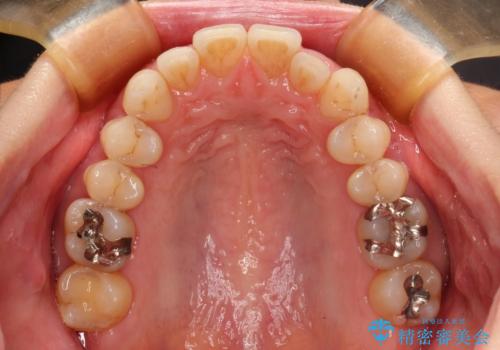

八重歯のインビザライン矯正治療

- 下顎の八重歯と、上下のクロスバイトを気にして来院された患者様です。

インビザラインを用い、下顎全体の後方移動、IPR(歯と歯の間を削る)と歯列全体を拡大させることで、歯並びを整えていくこととしました。